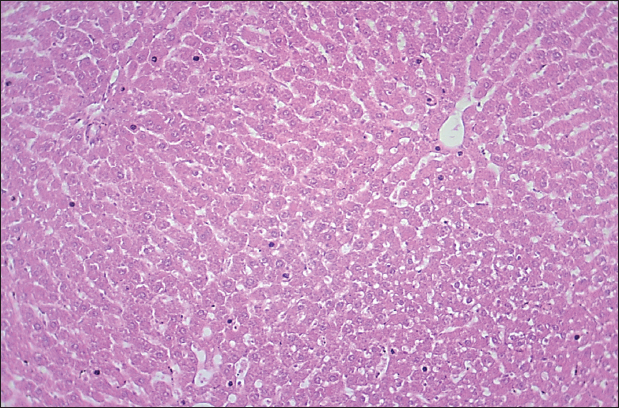

Fig. 1. Histological section of liver in rats of the control group. The section shows a normal histological structure for the hepatic sinusoid without any significant occupied lesion (H and E stain 100X).